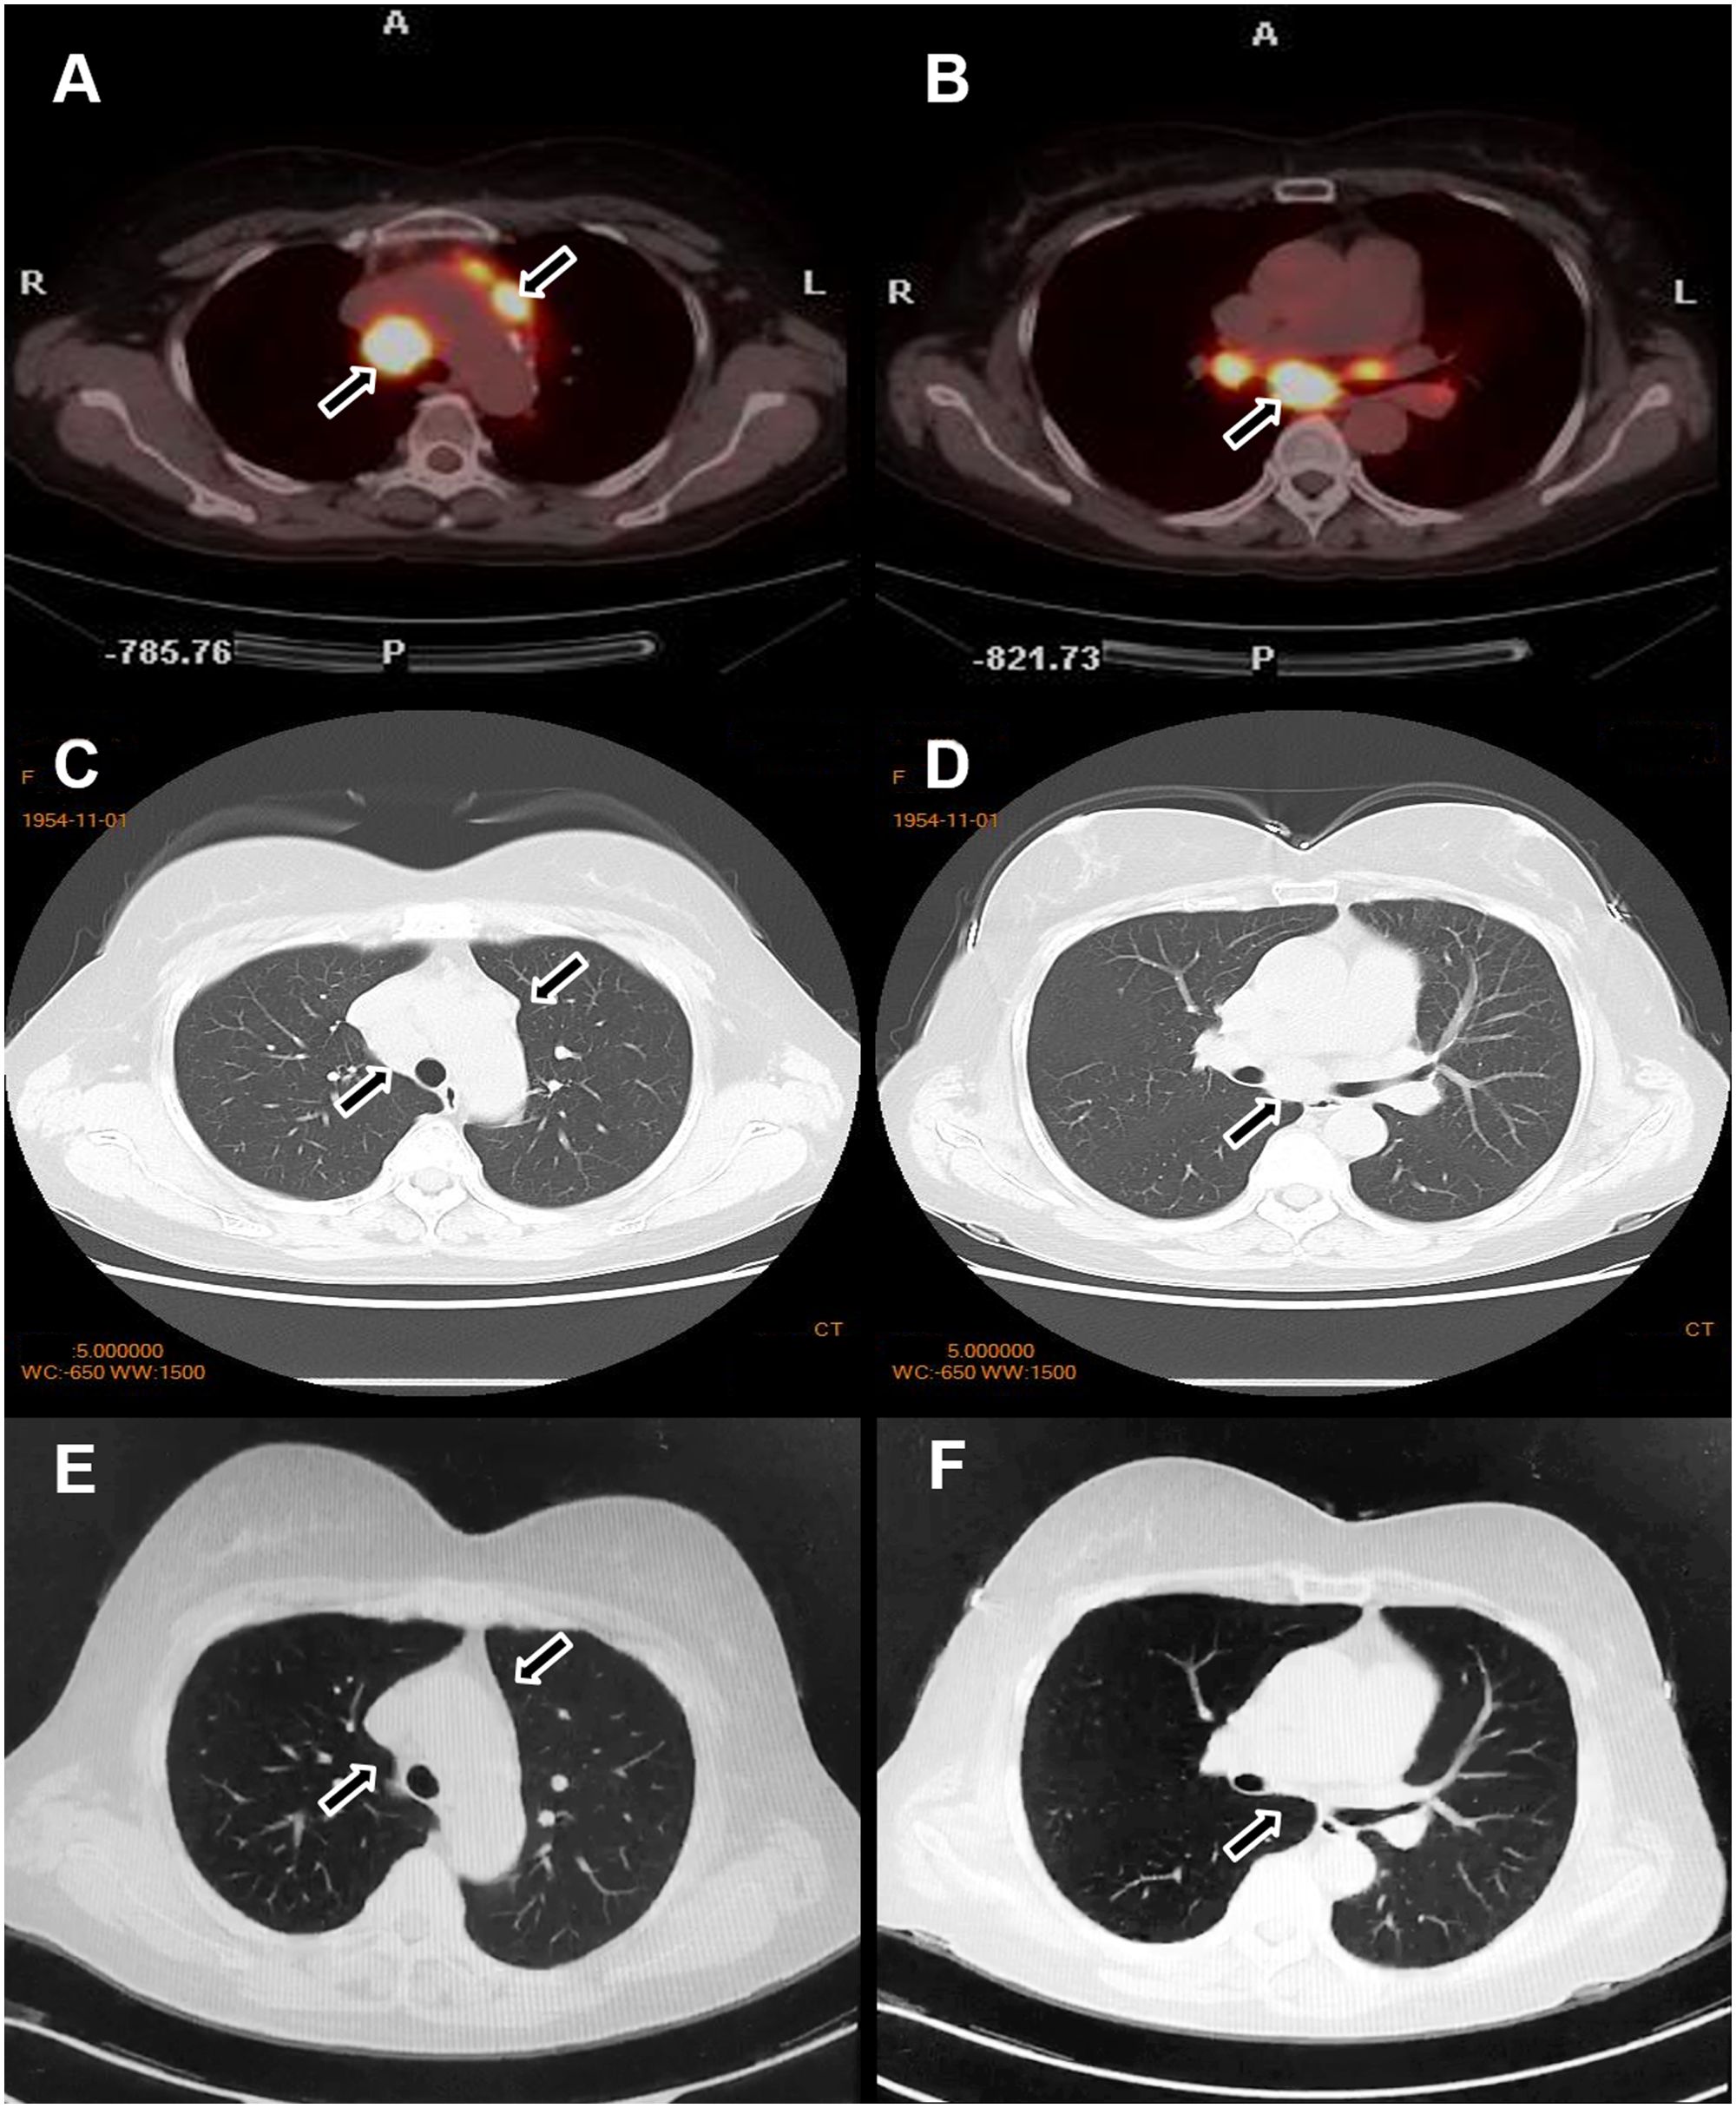

Chest CT revealed lymphadenopathy in the mediastinal and hilar regions. Subsequent PET-CT demonstrated multiple enlarged lymph nodes with increased ¹8F-fluorodeoxyglucose (FDG) metabolic activity in the right cervical, supraclavicular, bilateral hilar, and mesenteric regions (Figure 3A, and Figures 4A–D).

Figure 4

CT and PET scan images of the chest in panels A through F show different cross-sectional views, with arrows highlighting areas of interest. Panels A and B are PET scans with bright regions. Panels C through F are CT scans showing lung and surrounding structures, emphasizing specific regions with arrows for further examination.

Figure 4. Changes in the lymph nodes before and after treatment. Before treatment, PET-CT (A, B) and chest CT (C, D) revealed enlarged lymph nodes in the bilateral supraclavicular and hilar regions. After treatment, a marked reduction in the size of the lymph nodes was observed (E, F).

Although glucocorticoids are a first-line treatment for sarcoidosis, they are generally avoided in psoriasis due to the risk of transforming plaque psoriasis into more severe forms, such as erythrodermic or pustular psoriasis—particularly in cases of irregular medication adherence. Therefore, based on safety considerations, we opted to treat this patient with MTX, which effectively addresses both conditions. The patient was subsequently started on oral MTX 10 mg weekly. After three months of therapy, the cutaneous lesions of both psoriasis and sarcoidosis resolved completely. Repeat chest CT demonstrated significant regression of the enlarged pulmonary lymph nodes (Figures 4E, F). The patient was subsequently maintained on a low-dose MTX regimen (5mg/week). To date, the patient has remained clinically stable with no notable abnormalities.